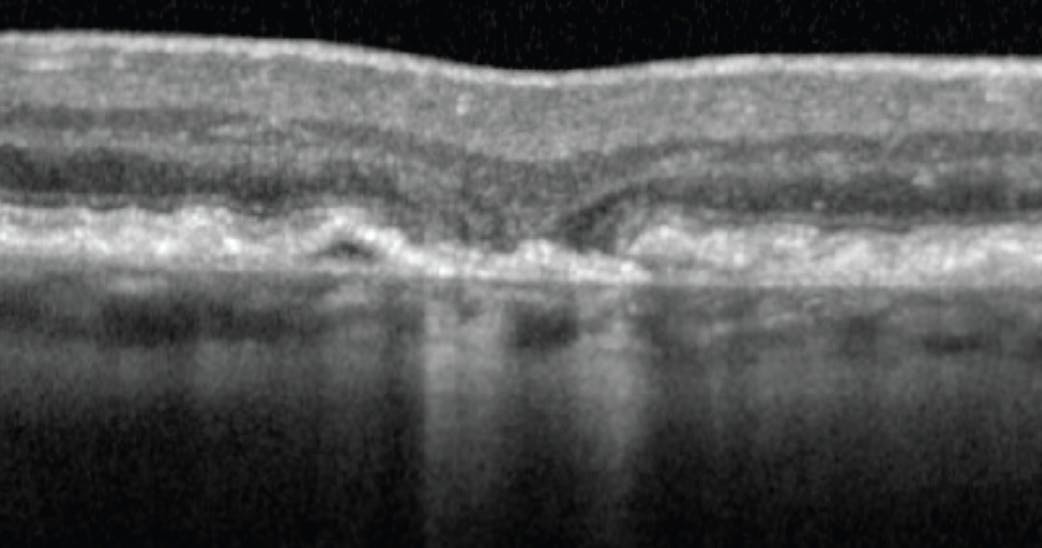

The signs observed in regions that went on to develop atrophy (and are required for nGA to be present) were subsidence of the outer plexiform layer and inner nuclear layer and/or development of a hyporeflective wedge-shaped band within Henle fiber layer, within the limits of the outer plexiform layer (Figure 2).4 Upon further analysis of data from the Laser in Early Stages of AMD (LEAD) study,5 we found that, following detection of nGA, the probability of progression to GA after 24 months was 38%. The development of nGA was associated with a markedly increased risk of progression to GA compared with those who did not develop nGA (adjusted hazard ratio, 78.1; P < .001). In addition, the development of nGA explained 91% of the variance in the time to GA development.4 Thus, this study demonstrated that nGA was a strong predictor of the development of GA, providing supportive evidence of its potential value as a surrogate endpoint in future trials for early stages of AMD.

Figure 2. nGA showing the required features of subsidence of the outer plexiform layer and inner nuclear layer and/or development of a hyporeflective wedge-shaped band within Henle fiber layer, within the limits of the outer plexiform layer.